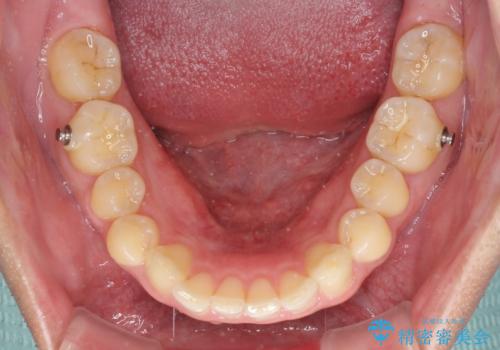

- 上顎前歯の突出感とすきっ歯を気にして来院された患者様です。

奥歯の咬み合わせを見ると、下顎に対して上顎が前方に位置していたため、補助装置により上顎歯列全体を後方に移動させ、その後インビザラインにて歯列全体を整えることとしました。